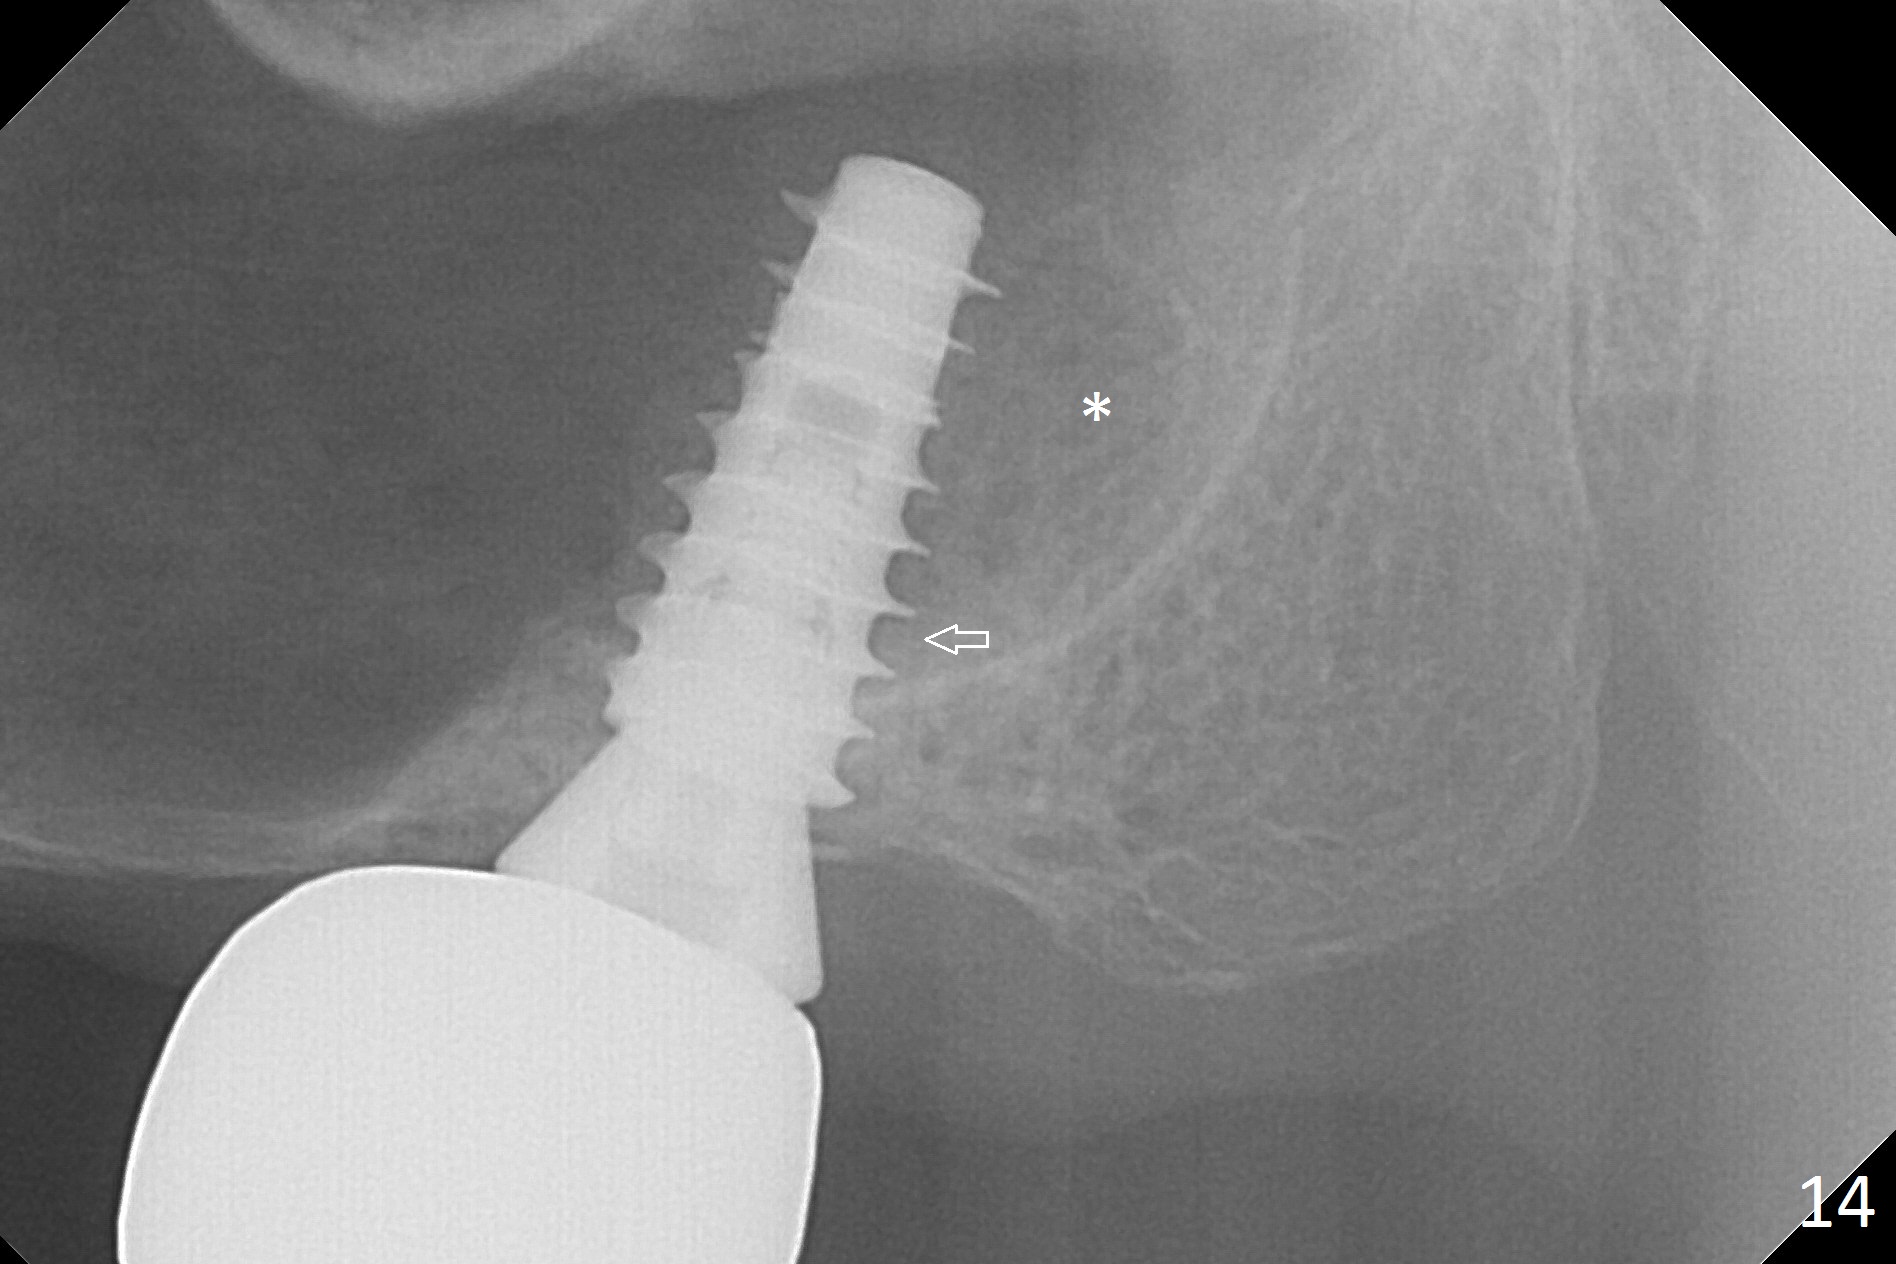

There is bone formation in the sinus distal to the implant 6 months post cementation (Fig.14 *) with the osseous tissue having grown into between the threads (arrow).